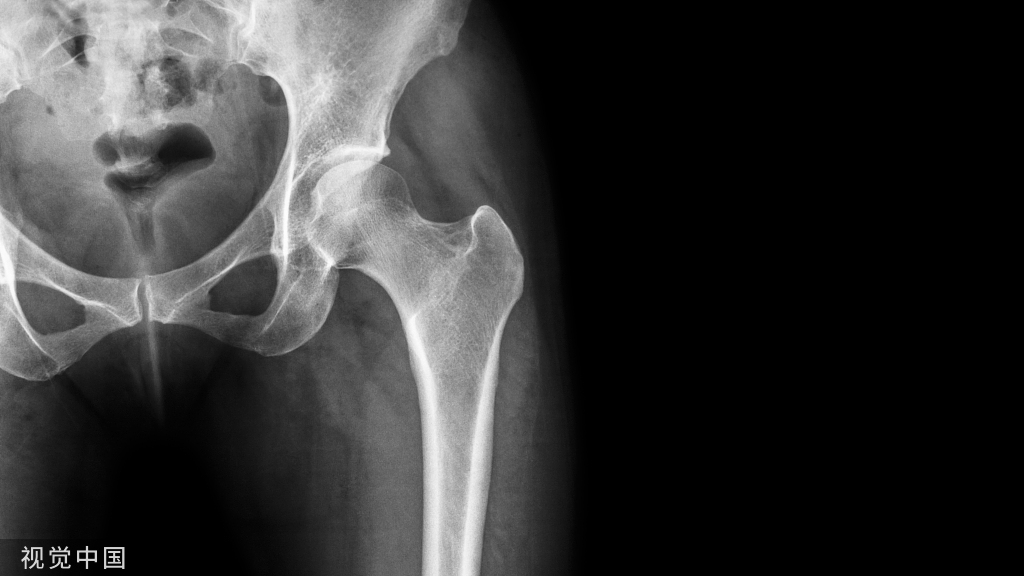

桡骨远端骨折是最常见的骨折之一——约占儿童骨折的 25% 和老年人骨折的约 18%。桡骨远端骨折呈双峰分布,在 18 岁以下和 65 岁以上的人群中骨折发生率相对较高。美国年发病率超过 640,000 例,仅 2007 年的医疗保险索赔就花费了 1.7 亿美元。

在桡骨远端骨折治疗中,患者和医生存在几个决策点。例如,对于桡骨远端骨折的治疗,存在保守和手术两种选择。尽管以固定或闭合复位的形式进行的保守治疗仍然是 65 岁以上人群中最普遍的治疗方式,但手术治疗(尤其是切开复位和内固定)正在增加。由于每种治疗方案和桡骨远端骨折的一般护理都有其自身的风险/收益概况,因此综合和理解各种治疗决策点背后的证据对于患者和外科医生就治疗决策进行讨论至关重要。